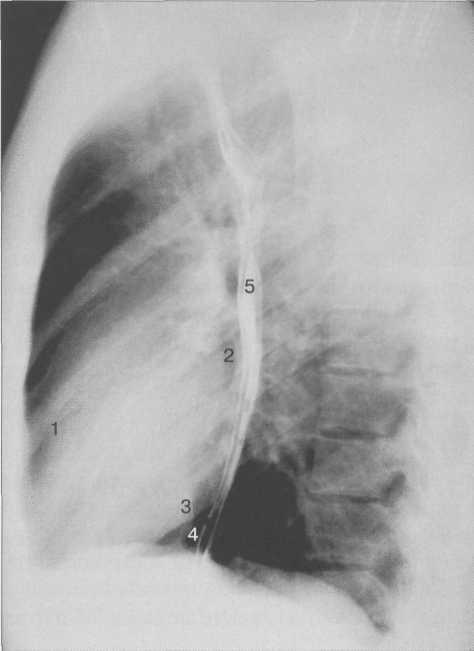

Рис. 9.25. Рентгенограмма грудной клетки. Левая боковая проекция.

1 — правый желудочек; 2 — левое предсердие; 3 — левый желудочек; 4 — нижняя полая вена; 5 — пищевод.

В левой боковой проекции (рис. 9.25) передний контур сердца образован правым желудочком. Задний контур сердца в верхнем отделе образован левым предсердием, которое вплотную прилежит к пищеводу, в нижнем отделе — левым желудочком, кзади от которого виден контур нижней полой вены. Правый желудочек образует с передней грудной стенкой угол, вершина которого находится на уровне наибольшего глубинного диаметра сердца. Протяженность прилегания правого желудочка к передней грудной стенке и левого желудочка к диафрагме должны быть одинаковыми.